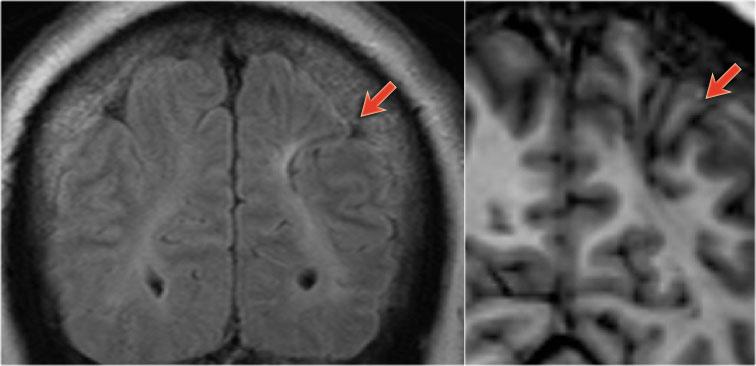

Các hình ảnh cho thấy loạn sản vỏ não khu trú điển hình.

Có hình ảnh dày vỏ não và mờ ranh giới chất xám/chất trắng trên chuỗi xung T1W (bên trái).

Ảnh FLAIR bên phải cho thấy tăng tín hiệu vùng dưới vỏ.

Các hình ảnh cho thấy bất thường tín hiệu vỏ não và dưới vỏ trên chuỗi xung T2W và FLAIR ở thùy thái dương trái, phù hợp với loạn sản vỏ não khu trú.

Lưu ý hình ảnh hồi hải mã tăng tín hiệu T2/FLAIR kèm teo nhỏ là hậu quả của xơ cứng thùy thái dương giữa, tức là bệnh lý kép.

Ảnh chuỗi xung T1W, T2W và FLAIR mặt phẳng axial của bệnh nhân nam 15 tuổi bị động kinh.

Lưu ý hình ảnh dày và tăng tín hiệu vỏ não hồi trán trên bên trái.

Ảnh FLAIR cũng cho thấy tăng tín hiệu ở chất trắng dưới vỏ.

Các dấu hiệu này điển hình cho loạn sản vỏ não khu trú.